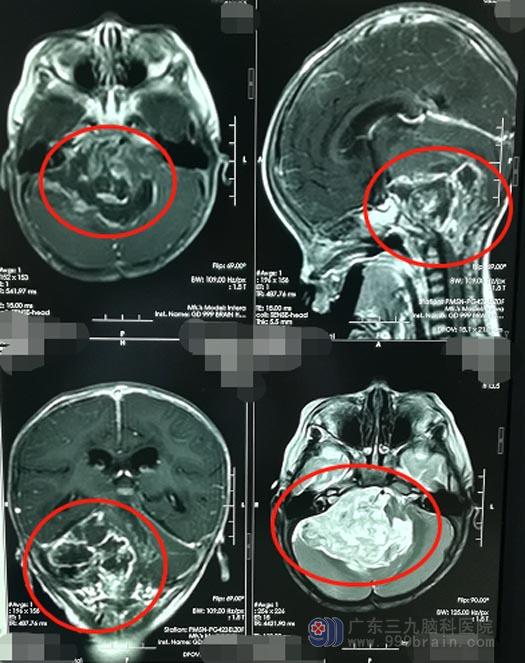

入住神经外五科后,主管医生李兴可立即为鹏鹏安排了一系列的专科检查,诊断结果为:脑干、四脑室、双侧小脑半球占位。

肿瘤所在的位置有丰富的血管和神经,此区域被称为手术禁区,稍有不慎,会损伤脑干、血管及神经,出现严重的并发症。但孩子病情非常危急,需要尽快手术,取得家属同意之后,由鲁明主刀在全麻下行“脑干、四脑室、双侧小脑半球肿瘤切除术+气管切开术”,术中见肿瘤侵蚀四脑室、双侧小脑半球、脑干,脑干已被肿瘤挤压至左侧,右侧三叉神经、面神经、后组颅神经均被肿瘤包裹;在显微镜下小心翼翼地将肿瘤全部切除,神经、血管均未受损伤。